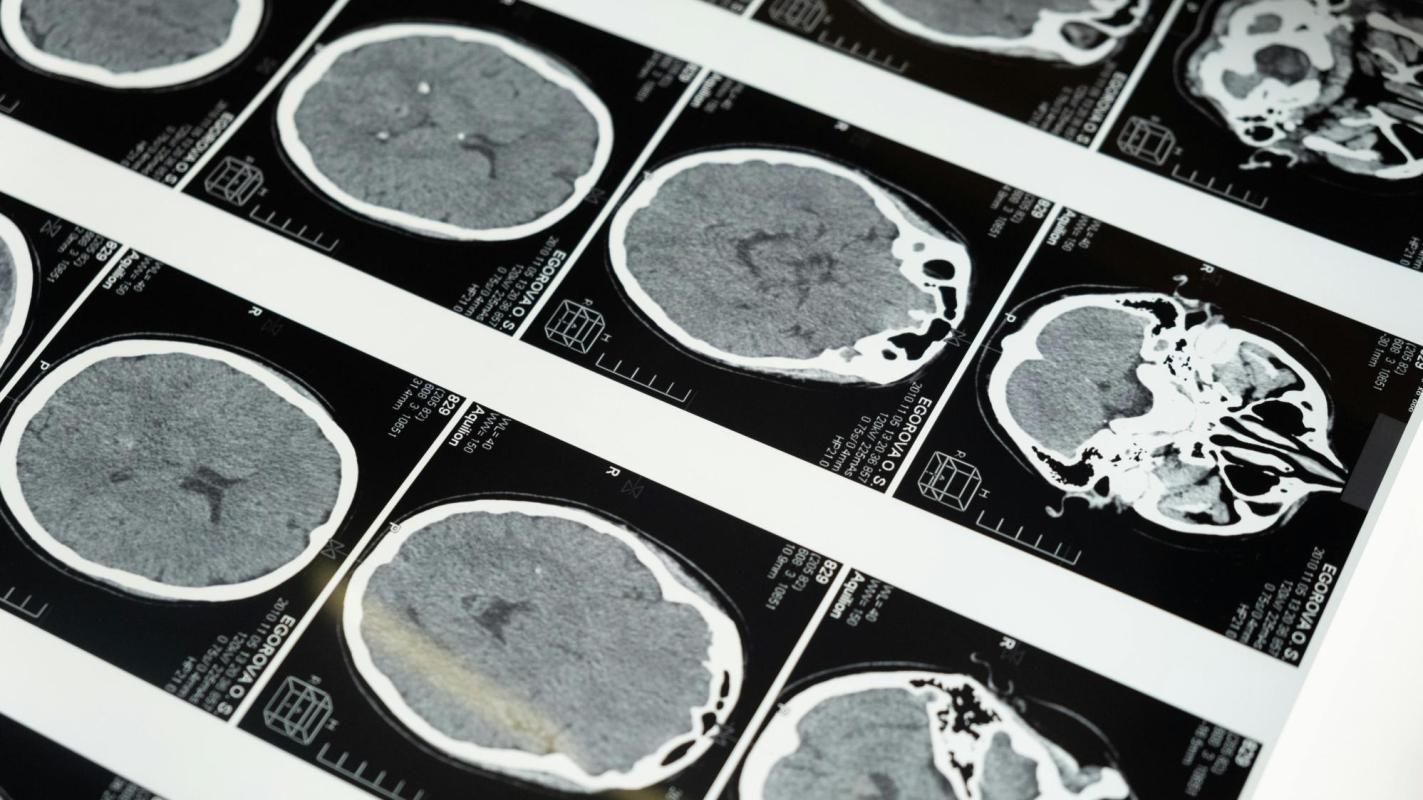

El ataque cerebrovascular (ACV) es hoy la principal causa de discapacidad en adultos en Chile y la segunda causa de muerte. Cada año, alrededor de 40.000 personas sufren un ACV en el país, y la mayoría no recibe un tratamiento oportuno, quedando con secuelas cuya carga médica, social y económica recae mayoritariamente en los hogares.

El análisis identifica 32.299 nuevos casos GES de ACV en 2023 sólo en el sistema público, donde cada 11 minutos una persona ingresa a urgencias por esta causa. Sin embargo, el acceso a trombólisis, el tratamiento que más reduce discapacidad y muerte, sigue siendo limitado: solo 1.329 pacientes reciben este procedimiento al año en hospitales de alta y mediana complejidad.